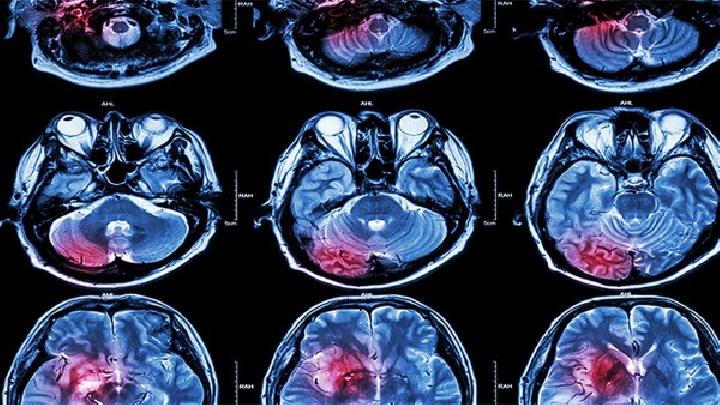

脑膜炎

专家讲解脑膜炎有什么症状